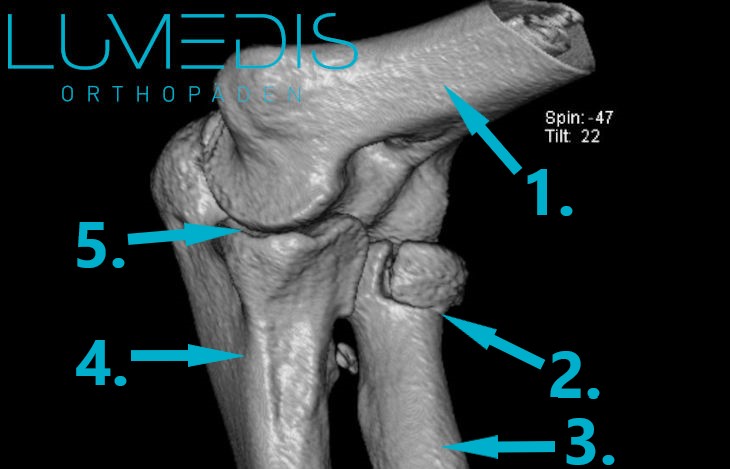

CT Bild einer Radiuskopffraktur

CT einer Radiusköpfchenfraktur

CT-Rekonstruktion einer Radiusköpfchenfraktur links